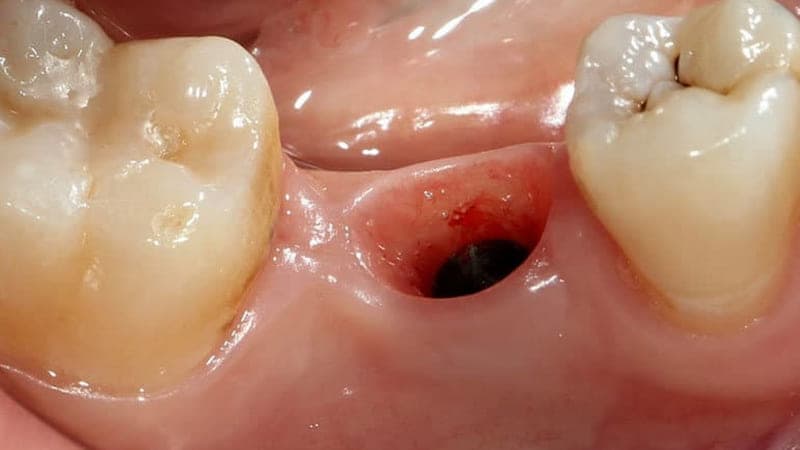

Nhổ răng khôn để lại lỗ: Bí quyết giảm sưng đau hiệu quả

Việc phát hiện một lỗ hổng tại vị trí răng khôn vừa nhổ là điều khiến nhiều người lo lắng. Tuy nhiên, đây là một phần hoàn toàn bình thường của quá trình lành thương. Tình trạng nhổ răng khôn để lại lỗ sẽ sớm được khắc phục nếu bạn hiểu rõ nguyên nhân và có cách chăm sóc đúng đắn. Bài viết này sẽ là cẩm nang toàn diện, cung cấp mọi thông tin bạn cần biết để xử lý vấn đề này một cách an toàn và hiệu quả.

2. Nhổ răng khôn bao lâu thì lấp đầy lỗ? Chi tiết quá trình lành thương

Thời gian để lấp đầy hoàn toàn lỗ hổng sau khi nhổ răng khôn có thể kéo dài vài tháng, tùy thuộc vào cơ địa và mức độ phức tạp của ca nhổ. Sau đây là những mốc thời gian gợi ý:

– 24 – 48 giờ đầu: Cục máu đông hình thành ổn định. Nướu có thể sưng và đau.

– Sau 1 tuần: Vết sưng và đau giảm đi đáng kể. Mô nướu bắt đầu tái tạo từ các mép của lỗ hổng.

– Sau 2 – 3 tuần: Lỗ hổng sẽ nông hơn và thu nhỏ lại rõ rệt. Bạn có thể vẫn thấy một vết lõm nhỏ trên nướu.

– Sau 1 – 2 tháng: Bề mặt nướu có thể đã đóng kín hoàn toàn. Tuy nhiên, xương bên dưới vẫn đang trong quá trình tái tạo.

– Sau 3 – 6 tháng: Xương mới đã lấp đầy gần như toàn bộ huyệt ổ răng. Lúc này, tình trạng nhổ răng khôn để lại lỗ mới được xem là kết thúc hoàn toàn.